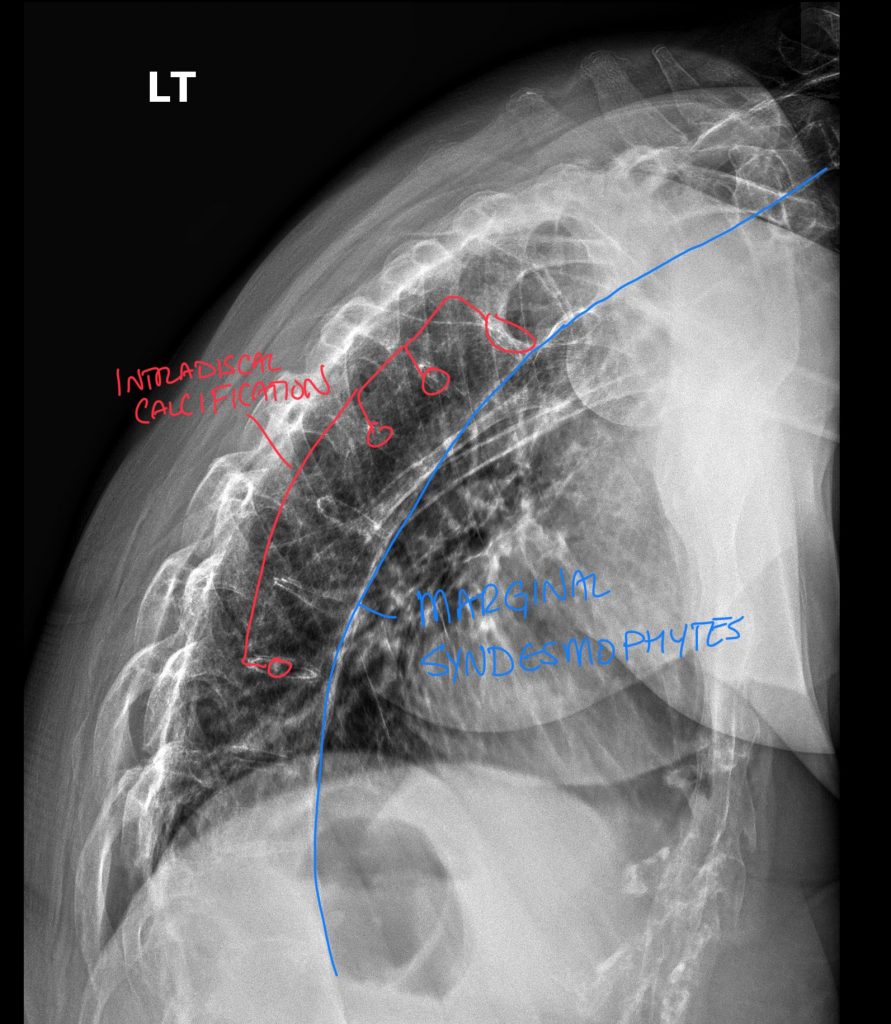

Lateral view of the thoracic spine.

Lateral view of the thoracic spine demonstrating marginal syndesmophytes, intradiscal calcification, and subtle findings of facet ankylosis and interspinous calcifications.

- Vertebral body squaring is the earliest and most reliable plain film sign, produced by inflammatory erosion of the normal anterior concavity

- Syndesmophytes appear as thin vertical ossifications along the outer annular fibers (distinguished from osteophytes, which are more horizontal and bulky)

- “Bamboo spine” — continuous vertical ossification bridging multiple disc levels — is pathognomonic for advanced AS on AP and lateral views

- Shiny corner sign (Romanus lesion) is better seen on lateral view: sclerosis at the vertebral body corner representing healed inflammatory erosion